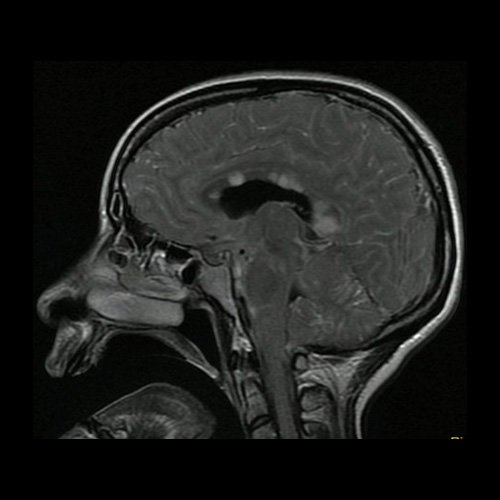

Día 2: RMI de cráneo ( T2 Flair – corte parasagital). Lesiones hiperintensas nodulares sólidas en cuerpo calloso en protuberancia.centros semiovales y cuerpo calloso con restricción en difusión.

La RMI muestra lesiones hiperintensas en T2 y FLAIR a nivel periventricular y subcortical, incluido el cuerpo calloso y el centro semioval, así como en la sustancia gris, incluida la corteza, los ganglios basales y el tálamo. Las lesiones infratentoriales en el tronco encefálico, el cerebelo y la médula espinal son comunes. Suelen tener realce con gadolinio. Difusión restringida.